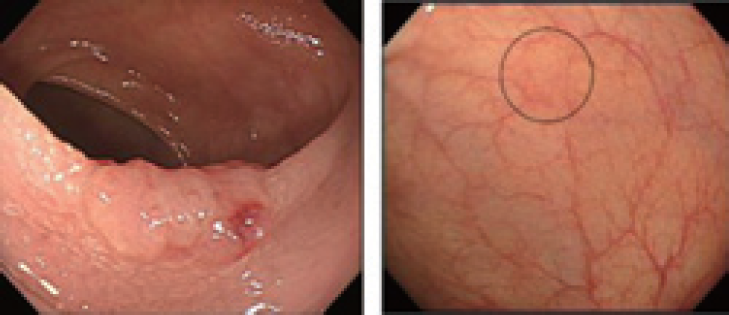

A2: 今まで2mmのがんというのは、ベテランの臨床医でも内視鏡を用いて見つけることは困難でした。それは、色でも形でも、正常な細胞とほとんど違いがないからです。蛍光を利用することによって、がんに特異的な分子をコントラストよくイメージングでき、形や色に変化の乏しい小さながんを検出できる可能性がでてきました。また、今までのがんの迅速病理診断は、がんであろうと思われる部分を切ってから、病理医が顕微鏡で診断していました。そのため、その間、患者さんは20~30分間待っているか、もしくは病理医のいない病院では、一度手術をした後、病理診断に切片を提出して、結果が出てから、また手術するという方法を取っていました。 私たちは、最良の診断というのは、スピードが早く、精度の高い診断であると考えています。今回の技術を利用すれば、蛍光による診断のため、小さながん細胞を見つけることができ、しかも診断スピードもはるかに速くなります。患者、病理医、外科医、3者の負担を軽減できると考えています。

▲小さいがんの参考例(左図は進行した腫瘍、右図の丸部分が初期の腫瘍、初期の腫瘍には、形や色の変化が少ない。

2)生体に内在する蛍光を用いた微小大腸腫瘍の検出

現在臨床において使われている内視鏡は大腸腫瘍の検出に有効であるが、主に形態的変化に基づき診断を行うため、形態変化の小さな微小腫瘍や平坦型腫瘍に対して十分な感度を持っているとは言えない5)。大腸内視鏡検査が形態変化の小さな腫瘍を見逃す頻度は高く、直径5~10mm、1~5mmの腺腫に対する見逃し率は、それぞれ13%、26%といわれている6)。我々は、形態変化に着目するよりも腫瘍化に伴う代謝変化に着目することが、内視鏡の診断能を上げるために有効と考えた。腫瘍は初期段階から代謝変化を伴い、また一般的に固形腫瘍は低酸素状態にあることが知られている7)。生体には数種類の内在性蛍光物質が含まれており、特にnicotinamide adenine dinucleotide (NADH)は細胞代謝に関連して蛍光強度が変化し、細胞が低酸素状態に陥るとNADH蛍光強度は上昇することが知られている8)。大腸癌の発生母地である大腸粘膜はNADHを豊富に含むため9)、大腸粘膜の腫瘍化をNADH蛍光強度の違いとして捉えられる可能性がある。ただ、生体内においてNADH蛍光を正確に測定するには、ヘモグロビンはNADHの励起光・蛍光を強く吸収するため、血液の影響を軽減・除去する必要がある。最近我々は、血液ヘモグロビンの光吸収の影響を除去可能な2波長励起蛍光イメージング法を開発し、ヒト大腸腺腫切除検体を用いてその高い診断能を報告した10)11)。2波長励起蛍光イメージング法は、NADH蛍光光量が最大となる波長を含むイメージ(Excitation:365nm)およびレファランス蛍光イメージ(Excitation:405nm)をそれぞれ取得後、画像間レシオ演算を行うことにより、腫瘍の血管密度や形状の影響の少ない腫瘍イメージングが可能な方法である(図2C,D)。すなわち、内視鏡的粘膜切除術を施行された大きさ3 mm以下のヒト大腸腺腫も高いS/N比で描出でき、in vivo においてラット微小大腸癌を検出可能であった。同方法は、蛍光レシオを擬似カラーとして表示する内視鏡システムを作製することにより比較的簡便に臨床応用可能であり、微小腫瘍の内視鏡的検出に有望である。

図2 生体内在性蛍光を用いたヒト大腸腺腫イメージング

A) 低酸素環境は固形腫瘍に共通した特徴である。がん組織はその発生初期から微小循環動態の欠陥等により恒常的に 低酸素状態にあるといわれている(J. Bull Cancer 2006;93:E73-80)。 B) ミトコンドリア呼吸鎖の模式図。細胞が 低酸素環境にさらされると細胞内NAD+/NADH redox状態は変化し、蛍光を持つNADHが増える。C) ヒト大腸腺腫 イメージング[a: 表面像(白色光)、b: 断面像(白色光)、c: 断面像(HE)、d: 断面像(NADH蛍光)、e: 断面像(レファレンス蛍光)、 f: 断面像(2波長励起蛍光イメージ:レシオ画像=NADH蛍光/レファレンス蛍光)]。2波長励起蛍光イメージング法を用いる ことにより、腫瘍の血管密度や形状の影響を受けない大腸腺腫イメージングが可能(C, D)。Scale bar = 1 mm